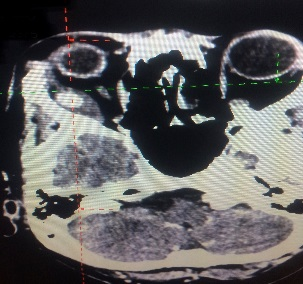

Orbital Tumour Surgery

Any tumour mass can occur within the bony socket of the eye. It may occur as a primary tumour or secondary tumour (metastatic disease). It is also essential to know the difference between a benign and malignant tumour. After discussing the symptoms and signs, a detailed clinical examination and some clinical tests, Dr Nazila will order for an imaging such as CT scan or MRI and advise for surgery.